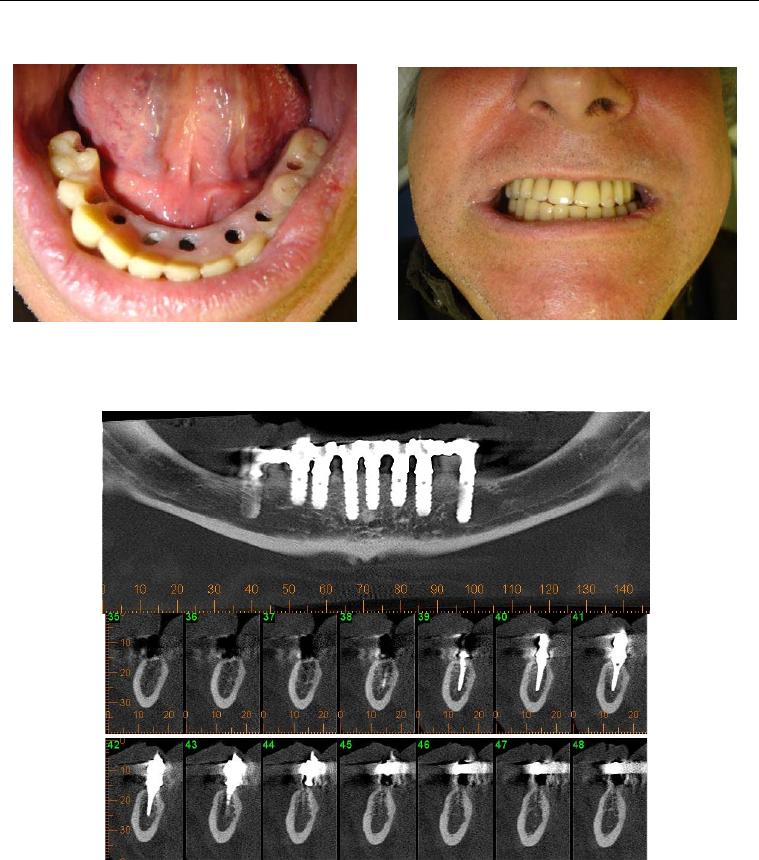

Foi no intuito de transpor estas dificuldades que se idealizou o sistema de

implante inicialmente conhecido como Wedge (figura 1) e que, após dez anos de